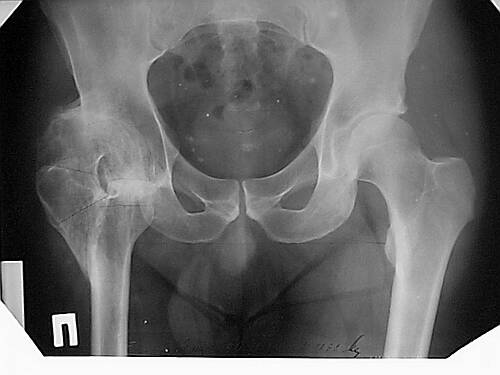

Уважаемые коллеги!Женщина, 35 летВ прошлом по поводу врожденного вывиха бедра перенесла операцию остеотомии по Шанцу

с удлинением правой ноги за счет бедра на уровне диафиза. В последнее время прогрессируют боли в правом тазобедренном суставе, порочное положение правой ноги, затруднена ходьба.Вопросы:1) Целесообразно ли эндопротезирование правого тазобедренного сустава?2) Целесообразный ли следующие действия: канал бедренной кости предполагаем вскрыть для введения ножки протеза на высоте угловой деформации, предполагаем низведение большого вертела с мышцами; протез будет подобран индивидуально, предполагается умеренная версия?В приложении рентгенограммы и трехмерная КТ.В цветном и более качественном варианте КТ размещена здесь

Похожий случай представляем на ретгенограммах. Операция выполнена в 1996 г.